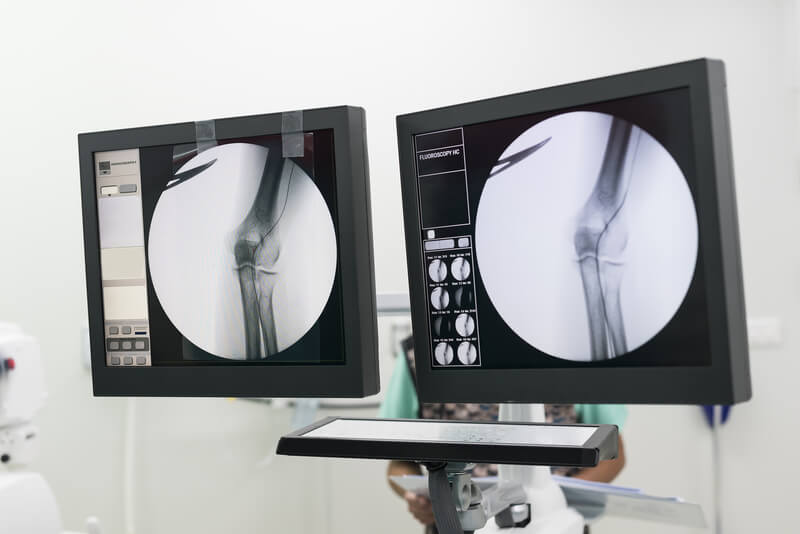

Diagnostic maneuvers consist of biopsy samples with needles and catheters under CT, ultrasound or fluoroscopic guidance.

Interventional procedures are usually carried out via a percutaneous access, puncturing the skin or main arteries and reaching the area to be treated with the use of guidewires, probes and catheters.